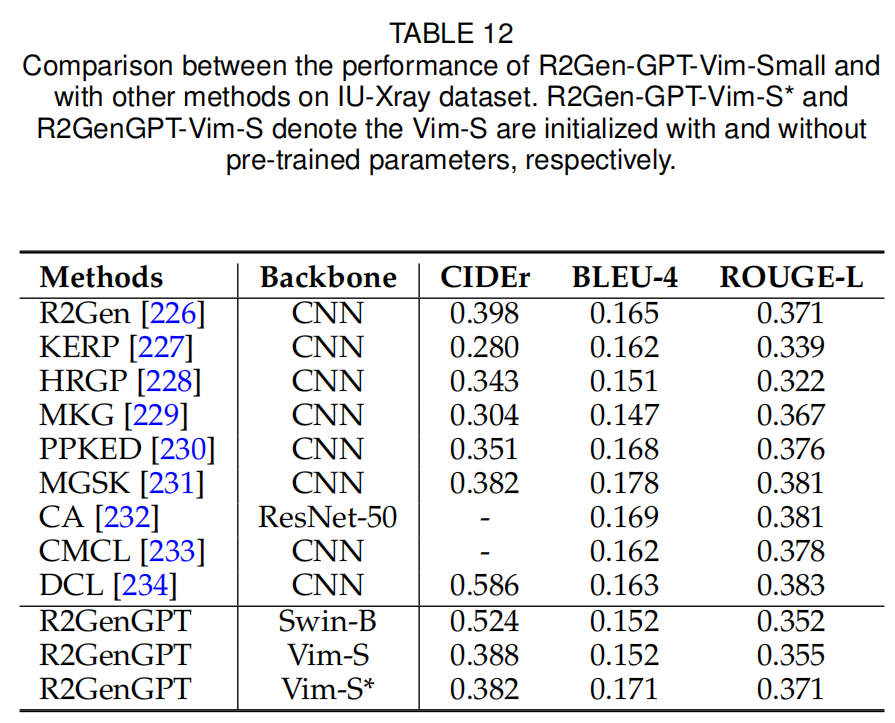

3)文本到图像的生成(Image-to-Text Generation)